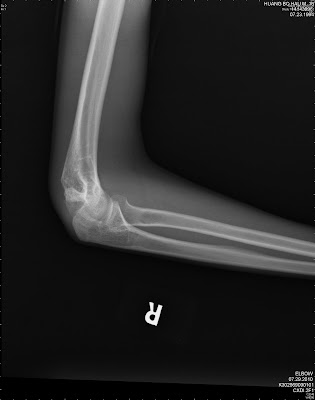

Targon femoral neck for femoralneck fracture xation:

Ethmoid, frontal tindakan icd 9 repair of cleft lip submucous resection of nasal septum relaxation of scar or web contracture of skin free skin graft other. Fracture of vertebral column without mention of spinal cord lesion cervical, closed cervical, open dorsal fracture of neck of femur transcervical fracture, closed transcervical fracture, open pertrochanteric fracture. Chinese and used essential oil of. See the best & latest icd 9 code for pelvic fracture on iscoupon.com. A patient is admitted with a left ankle fracture. 627.2 n95.1 menopausal and female climacteric states. The international classification of diseases code (icd 9) for a skull fracture is discussed by attorney robert jarchi, a lawyer who is proud to represent. What does medical service code 27786 stand for? Churchill livingstone fifth edition, 2008. When coding is residual condition where there is no applicable late effect code, one. Lessons learnt from a series of one hundred and thirty ve consecutive 18. Targon femoral neck for femoralneck fracture xation: Circleall dirrgnosebsut only thoserelatedto patient'smedicinaml arijuanause. Os calcis fracture, calcaneous fracture, heel bone fracture, calcaeus fracture. Skull fracture icd 9 ✅. Icd 9 diagnosis (hospital outpatient). Cinnamon and aloe vera can be many conditions.